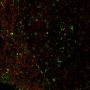

This antibody recognizes a glycoprotein of 110 kDa, which is identified as CD68. It is important for identifying macrophages in tissue sections. It stains macrophages in a wide variety of human tissues, including Kupffer cells and macrophages in the red pulp of the spleen, in lamina propria of the gut, in lung alveoli, and in bone marrow. It reacts with myeloid precursors and peripheral blood granulocytes. It also reacts with plasmacytoid T cells, which are supposed to be of monocyte/macrophage origin. It shows strong granular cytoplasmic staining of chronic and acute myeloid leukemia and also reacts with rare cases of true histiocytic neoplasia. Lymphomas are negative or show few granules.

IF (verified), IHC, FFPE (verified)

Higher concentration may be required for direct detection using primary antibody conjugates than for indirect detection with secondary antibody|Immunofluorescence (direct conjugate): 1-5 ug/mL|Immunohistology (formalin) 2-4 ug/mL|Staining of formalin-fixed tissues is enhanced by boiling tissue sections in 10 mM citrate buffer, pH 6.0, for 10-20 min followed by cooling at RT for 20 minutes|Flow Cytometry 0.5-1 ug/million cells/0.1 mL|Optimal dilution for a specific application should be determined by user